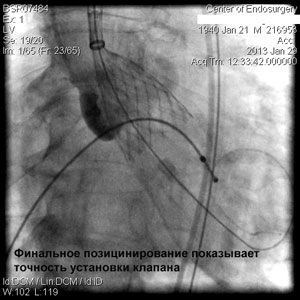

Через прокол (или маленький разрез) в артерии, в сжатом состоянии проводят искусственный клапан, который расширяется при его установке на месте поврежденного аортального клапана. После раскрытия клапан начинает функционировать и восстанавливает полноценную и нормальную работу аорты.